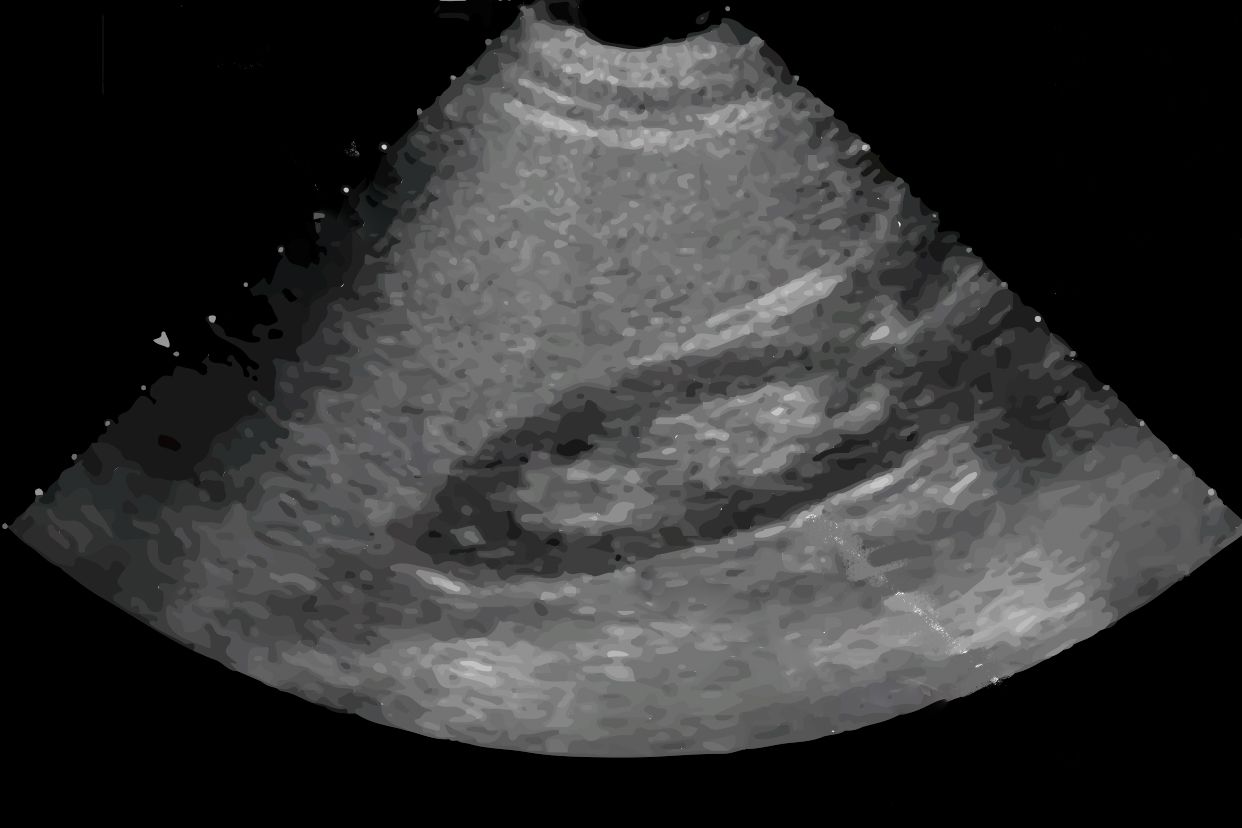

符合脂肪肝声像图一般是指肝脏检查时出现脂肪肝的超声影像,超声影像通常会提示肝内回声增粗、细密、肝内静脉显示不清等,脂肪肝患者还可能会出现肝脏轻度、中度的肿大。

脂肪肝声像对诊断脂肪肝是有一定的帮助,还可以评估脂肪肝的轻重程度。